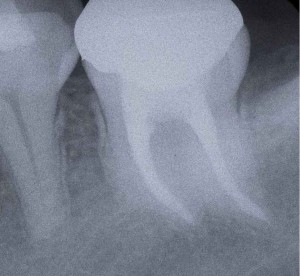

そこそこ細くて弯曲している根管より遙かに難しいのが、写真のような「太くて弯曲している根管」なのです。